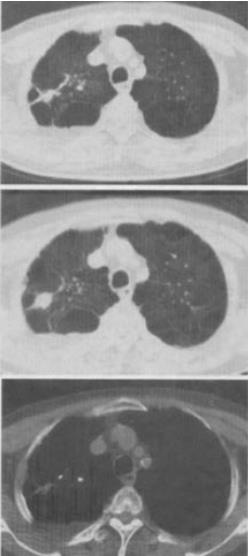

患者男,76岁,气喘数年,胸痛1个月余,结合图像,最可能的诊断是()。

A、右上肺结核球

B、肺间质纤维化

C、右上肺瘢痕癌

D、右上肺错构瘤

E、右上肺肉瘤

C